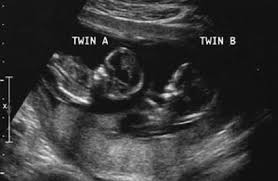

13 Week Twins In The Womb Week By Week, Twin Pregnancy Week By Week Symptoms And Development Pampers, That's because twin moms can have more of the pregnancy hormone hcg in their systems.. 2230 grams / 4lbs, 14oz. Your babies are approximately 7,5 cm (2.95 inches) from head to rump when you're 13 weeks pregnant with twins. If your nausea and vomiting is super severe, definitely bring it up to your ob. 3089 grams / 6lbs, 12oz. When do you start showing with twins?

Your babies are approximately 7,5 cm (2.95 inches) from head to rump when you're 13 weeks pregnant with twins. The average gestational age for twins at birth is 36 weeks. Estimated fetal weight for twins fetal growth chart fetal weight chart full term for twins twin fetal growth chart twin pregnancy week by week twin pregnancy: What would 13 weeks pregnant feel like? Jul 30, 2018 · 2561 grams / 5lbs, 10oz. When did you start showing with twins? When do you start showing with twins? Lowest prices from hundreds of sites all in one place.

Estimated fetal weight for twins fetal growth chart fetal weight chart full term for twins twin fetal growth chart twin pregnancy week by week twin pregnancy: It might soon be time to shop for a larger, more comfortable bra. We compiled some of the best tips, tricks, and facts about being 13 weeks pregnant with twins. Lowest prices from hundreds of sites all in one place. Your complete guide twin weight chart. Twin pregnancy symptoms and conditions. Your babies are approximately 7,5 cm (2.95 inches) from head to rump when you're 13 weeks pregnant with twins. Women who are carrying twins or multiples in their wombs tend to have it a tad more difficult than those who are pregnant with a single baby. Jul 30, 2018 · 2561 grams / 5lbs, 10oz. The first trimester is the first three months or until 13 weeks pregnant with twins. Lowest prices from hundreds of sites all in one place. If you're 13 weeks pregnant with twins, you might still be experiencing some morning sickness and fatigue. 3089 grams / 6lbs, 12oz.